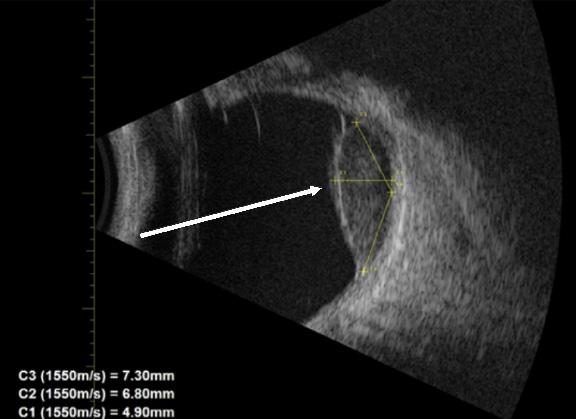

with a palpable foreign body, but nothing was visualized at the urethral meatus. Plain radiography was interpreted as normal with no visualized foreign body. Lab work and urinalysis were also normal. Clinicians using POCUS were able to visualize a linear hyperechoic object within the urethra (Image 1). Urology was consulted and took the patient to the operating room (OR) for removal with cystoscopy. In the OR a rolled-up piece of plastic was identified three centimeters into the urethra and was successfully removed. The patient was discharged without complication the following day.

Point-of-care ultrasound provides multiple benefits while avoiding many of the drawbacks of more standard evaluation. Plain radiography can be helpful and performed at the bedside if needed; however, it is only useful if the object in question is radiopaque. As our case series demonstrates, POCUS is capable of viewing objects that are both radiopaque and radiolucent. Additionally, plain radiography shows a twodimensional picture while POCUS can be used to obtain views in multiple planes to better map out an object’s shape, location, and orientation. While CT provides a detailed, three-dimensional picture, it requires patient cooperation, as well as a substantial exposure to radiation. This is potentially exacerbated by the fact that some of these patients may have similar repeated presentations, especially if being driven by a behavioral problem or sexual gratification. Additional considerations are cost and time to obtain the imaging, often requiring transporting the patient to another area for imaging.

While POCUS does not provide the same level of detail as a CT, it does allow visualization of the object as well as provide information regarding shape, orientation, and location. Point-of-care ultrasound images can be obtained quickly, and the images are interpreted by the emergency physician, expediting imaging results. Additional benefits of ultrasound include avoiding radiation, lower cost, and not requiring the patient to remain still. Point-of-care ultrasound certainly has a role as a diagnostic tool for urethral foreign bodies, but it is rarely used in this capacity.